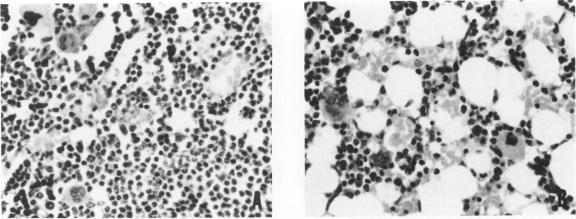

Injection of streptococcus group A cell wall-derived peptidoglycan polysaccharide into a subcutaneous air pouch causes local outpouring of neutrophils and macrophages and distant hemopoietic proliferation in spleen and bone marrow. Cyclosporine A (CyA) suppressed neutrophil accumulation and all cell lines of hemopoiesis. trans-1,2-Bis(5-amidino-2-benzimidazolyl)ethene (BBE) also interfered with neutrophil exudation, yet reduced only the erythroid component of the hemopoietic process. The ethane analogue of BBE, on the other hand, did not prevent neutrophil emigration, but held down splenic erythropoiesis and myelopoiesis. All three compounds stimulated streptococcus group A cell wall-derived peptidoglycan polysaccharide uptake by pouch macrophages. CyA being the least active, BBE and its ethane analogue also produced a shift of wear-and-tear pigment from large numbers of small splenic macro-phages into small numbers of large macrophages. The pouch model is very useful in the study of anti-inflammatory compounds and has furnished the first evidence of CyA interference with massive neutrophilic infiltration and with hemopoietic signals.

将A组链球菌细胞壁衍生的肽聚糖多糖注射到皮下气囊中会导致中性粒细胞和巨噬细胞在局部渗出,并使脾脏和骨髓出现远处造血增殖。环孢素A(CyA)抑制中性粒细胞聚集以及所有造血细胞系。反式-1,2-双(5-脒基-2-苯并咪唑基)乙烯(BBE)也干扰中性粒细胞渗出,但仅减少造血过程中的红系成分。另一方面,BBE的乙烷类似物并未阻止中性粒细胞迁移,但抑制了脾脏的红细胞生成和骨髓生成。这三种化合物均刺激气囊巨噬细胞摄取A组链球菌细胞壁衍生的肽聚糖多糖。CyA活性最低,BBE及其乙烷类似物还使大量小脾脏巨噬细胞中的损耗色素转移到少量大巨噬细胞中。气囊模型在抗炎化合物研究中非常有用,并且提供了CyA干扰大量中性粒细胞浸润和造血信号的首个证据。